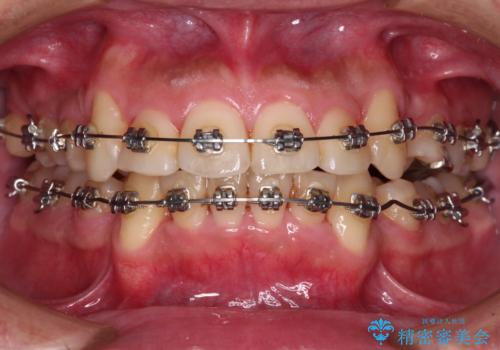

- メタルブラケット

右上第一小臼歯は歯根癒着により移動せず、左上第二小臼歯は移動はするものの非常に動きが鈍かったため、抜歯したスペースを閉じるまでに非常に時間がかかってしまいました。

患者様には辛抱強く治療にお付き合いいただき、すっきりとした口元に仕上げることができました。